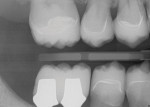

A 51-year-old male patient presented to the practice. His chief concern was that he was having great difficulty chewing, but he also expressed dissatisfaction with the esthetics of his smile. He reported experiencing advancing tooth wear and deterioration as well as the loss of several teeth. There were no significant complicating medical factors in his history; however, he did report longstanding hearing loss and tinnitus. The clinical evaluation revealed an overclosed VDO and minimal display of badly worn teeth (Figure 1 through Figure 3), and a CBCT analysis revealed moderately advanced degenerative changes of the TMJs without evidence of present activity (Figure 4) as well as an adequate oropharyngeal airway (Figure 5).6

The final restorations were fabricated by the laboratory to exactly duplicate the wax-up blueprint in reinforced glass-ceramic (Figure 18 through Figure 23). To maximize the bond strength to the ceramics, the crown margins were carefully positioned in order to preserve a wide band of enamel (Figure 19).11 The case was completed in 2014, and all of the patient's follow-up visits to date have revealed a stable dentition with no evidence of further wear or deterioration.